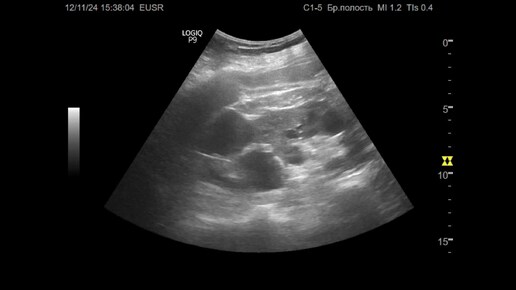

Ультразвуковая диагностика (УЗИ). Доктор Иогансен. Видеопримеры. Выпуск 105. Поликистоз почек.